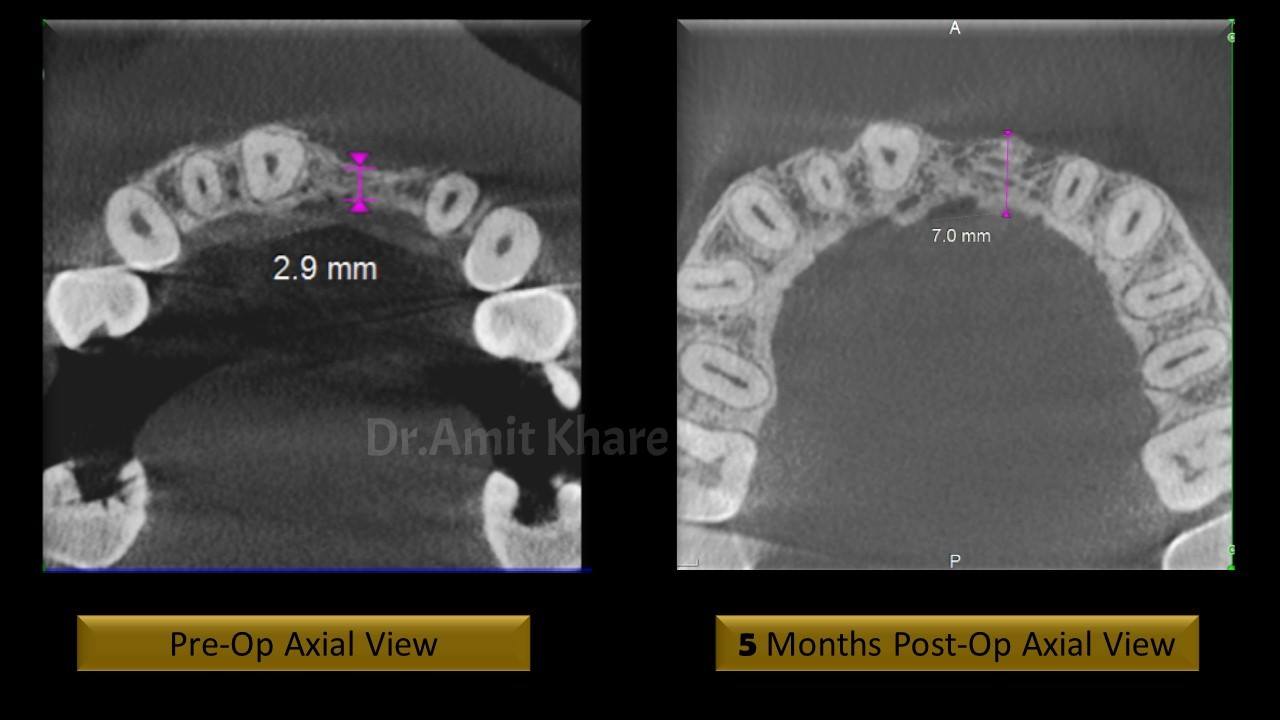

Clinical and Radiological investigation reveals deficient bone to receive an implant

Autogenous ‘Symphysis Block Graft’ was planned to regenerate the lost bone